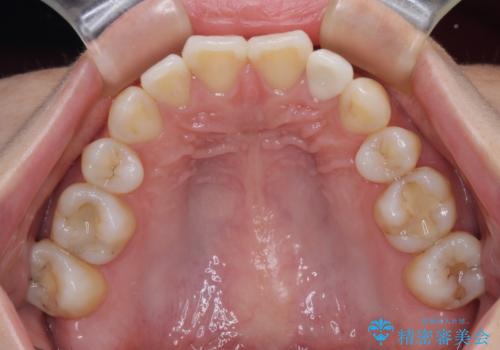

根管治療後速やかに痛みが消退し、6ヶ月後のレントゲン写真では、根尖部の病変がほぼなくなっていることが分かりました。